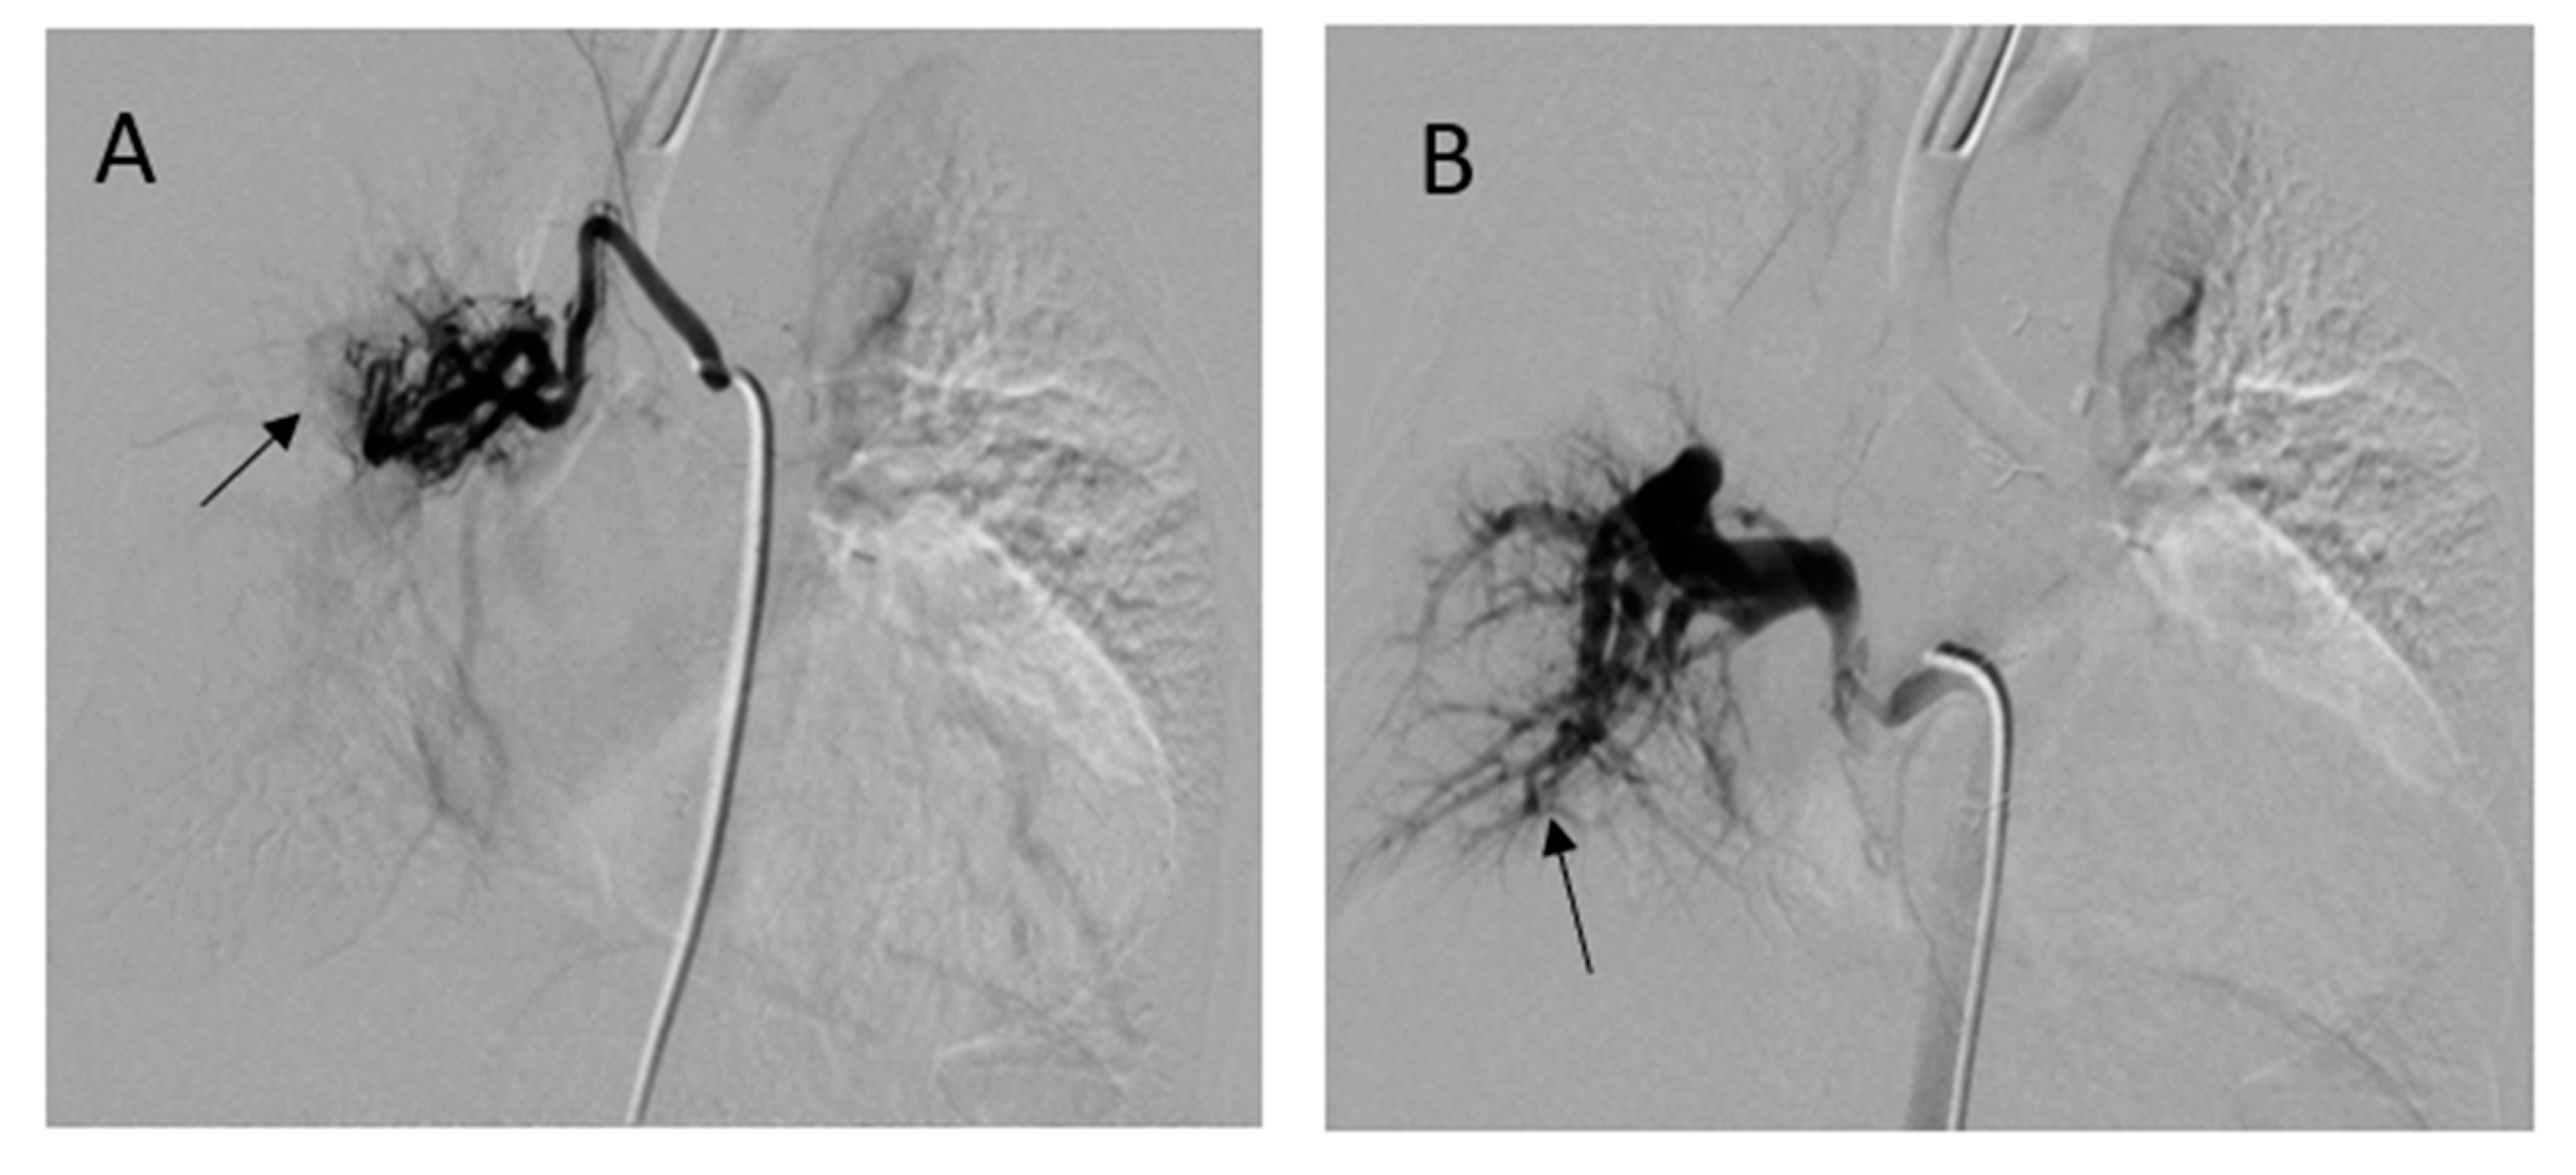

She underwent computed tomography (CT) angiogram of the chest which showed occluded right BT shunt and MAPCAs with a variable degree of stenosis supplying to bilateral lung fields (Figure 3). There were hypoplastic branch pulmonary arteries which were of ductal origin. She underwent cardiac catheterization and balloon angioplasty and stenting of MAPCAs. Her SpO2 increased from 60 to 75%. Selective angiogram of MAPCAs on the right side with digital subtraction showed the abnormal distal arborization of pulmonary vasculature suggesting vascular remodeling and PVD in the right upper lobe (Figure 4A) compared to the lower lobe (Figure 4B). She was discharged on aspirin, iron supplementation, and oxygen. On the latest follow-up 3 months after the interventional procedure, her functional capacity improved from NYHA class III to Class II.

Figure 4. Digital subtraction angiography of selective MAPACs. (A) MAPCA supplying the right upper lobe showed absence of normal arborization (arrow) and (B) the lower MAPCA showed relatively normal distal pulmonary vascular arborization pattern in right lower lobe (arrow).